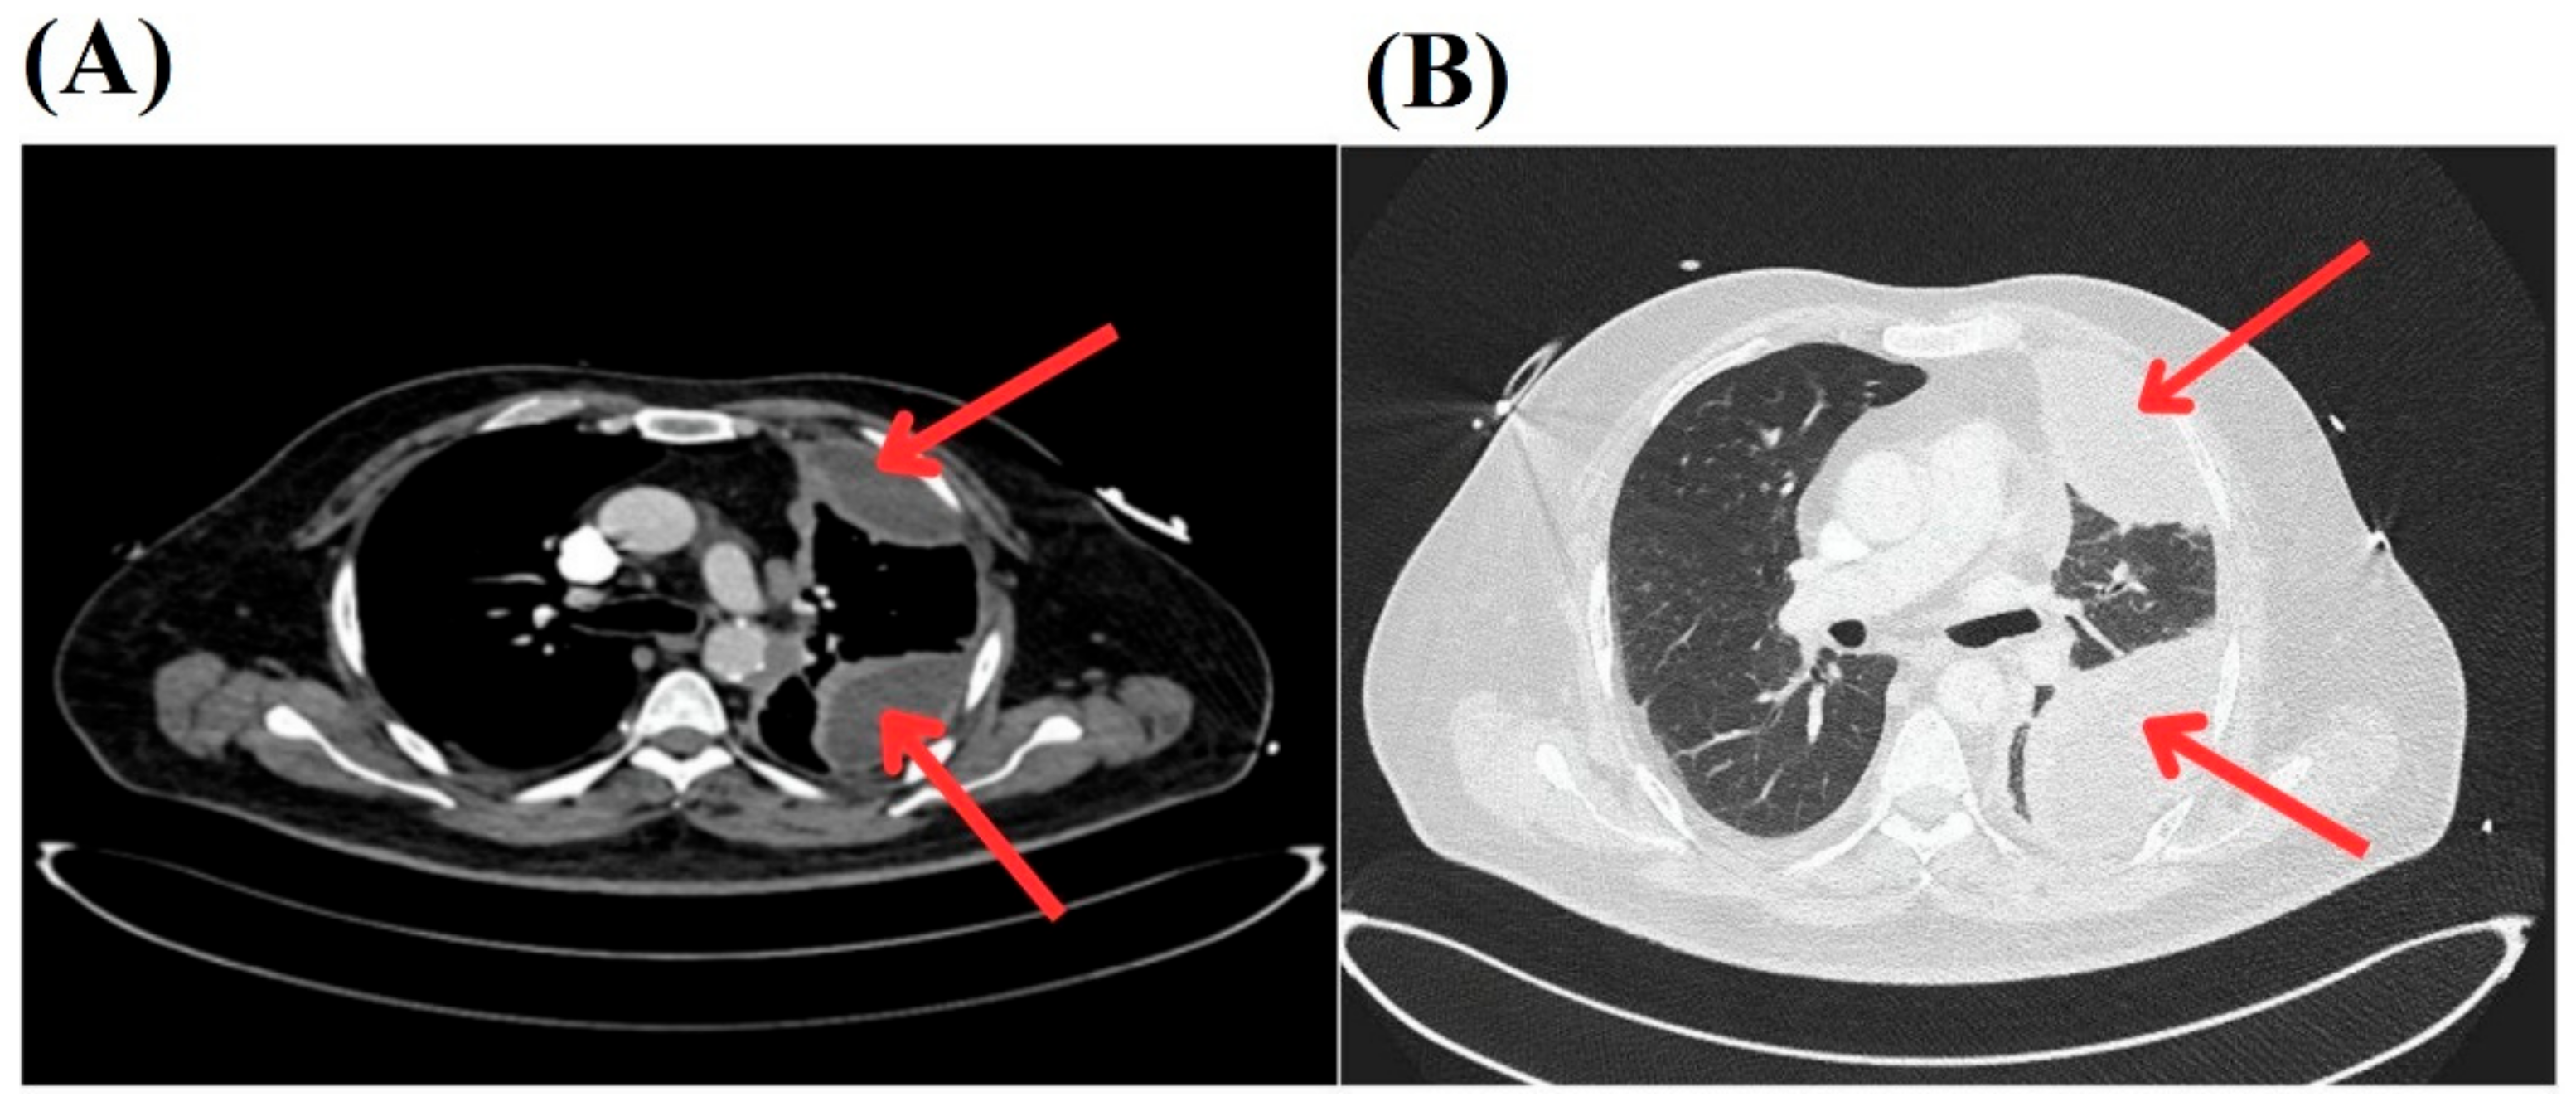

2. Case Presentation